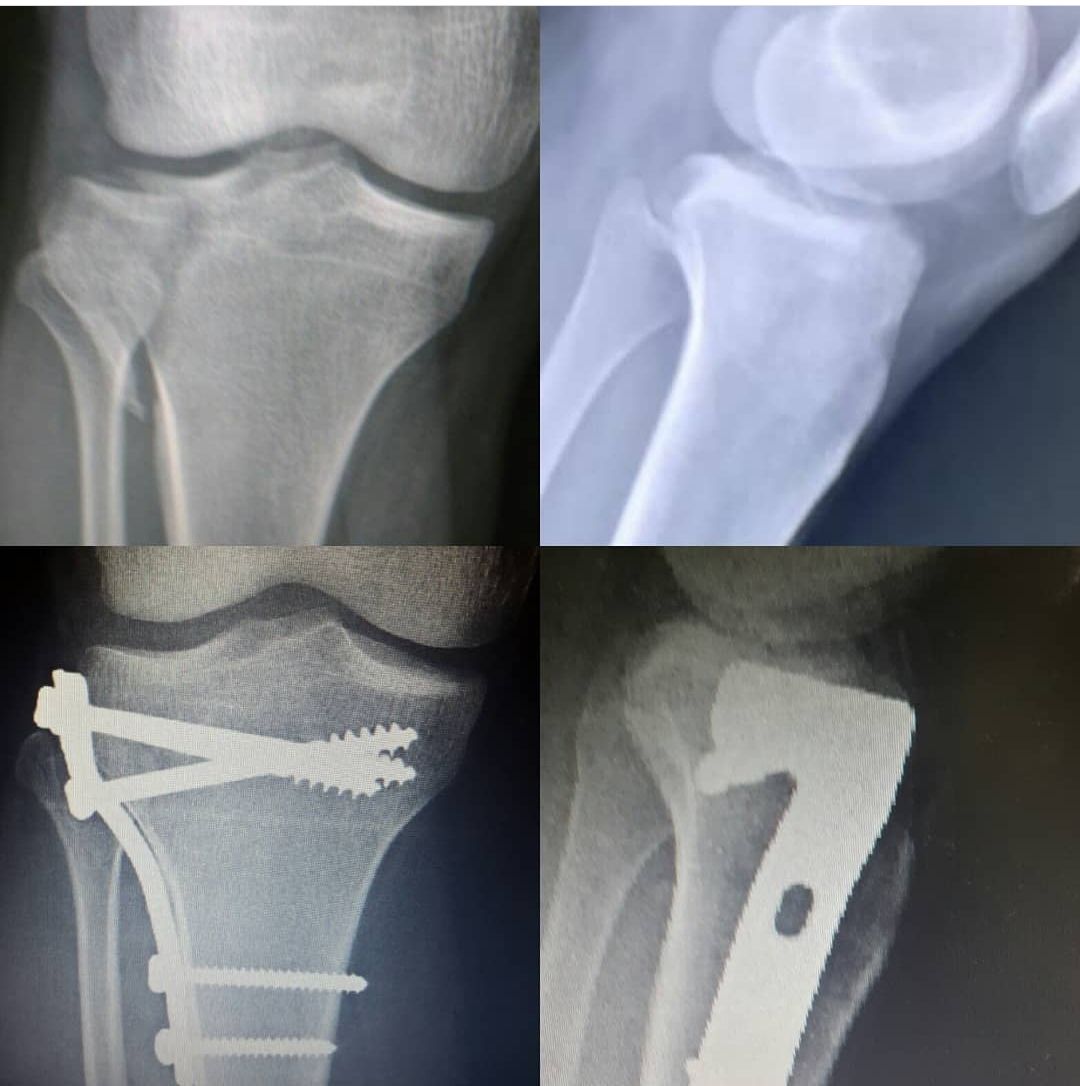

Querido paciente, soy Traumatólogo y Ortopedista egresado del Hospital Central de la Universidad Autónoma de San Luis Potosí, donde me especialicé a tratar todo tipo de problemas en el sistema musculoesqueletico, desgaste, fracturas, luxaciones, lesiones ligamentarias de (hombro, codo, mano, muñeca, columna, cadera, rodilla, pie y tobillo)

Posteriormente hice una Alta Especialidad en el Hospital de la Cruz Roja Mexicana de Mérida Yucatán, donde aprendí a tratar patología específica y compleja de pie y tobillo ( desgaste de tobillo, espolón Calcaneo y Fascitis plantar, Hallux Valgus (Juanetes), Pie plano del niño y del adulto, pie cavo, deformidades de los dedos menores del pie, pie diabético, artropatía de charcot, lesiones del tendón de Aquiles, lesiones deportivas.

Tuve la oportunidad de estar en "Centre Hospitalier de Dax - Côte d'Argent" en FRANCIA, donde aprendí a utilizar los mejores y más novedosos materiales para tratar todo lo relacionado a fracturas, columna y artroscopia.